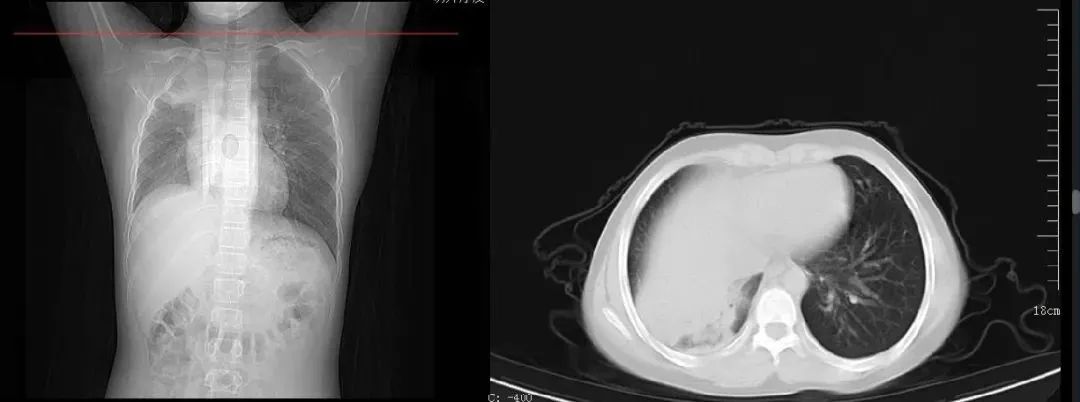

案例二,12歲,男性,確診病例

胸片顯示一側肺部組織大面積變白

影像所見: 右肺內帶見片狀軟組織樣高密度影,右肺野內亦可見片狀高密度影,右側肋膈角變淺變鈍,膈面模糊??紤]右肺部分不張伴胸腔積液可能。